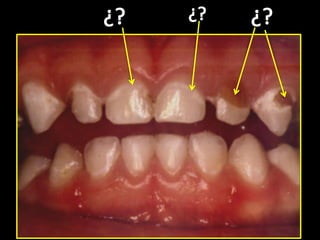

Menor de 3 años con

cualquier evidencia

de caries en

superficie lisa

3, 4, 5 años con

superficie lisa de

incisivo central

Las primeras lesiones no son cavitadas

a medida que pasan los años

aparecen más lesiones cavitadas